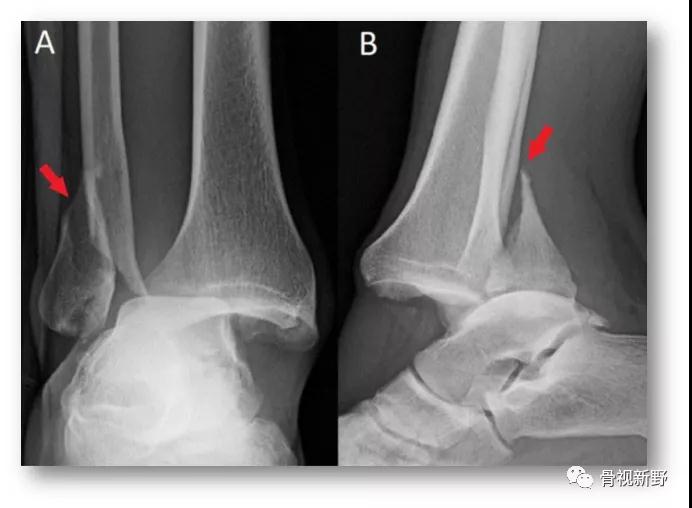

手法复位前X光片

氯胺酮基础麻醉下,患者屈膝位,踝关节背屈位牵引,通过足的旋后、内旋给距骨施加一个前向力,以大体复位踝关节(此时如沿腓骨远、近端触诊,会发现腓骨仍然交锁于胫骨后方)。腓骨解锁:一手手指置于腓骨干后内侧面并向前、外推挤,另一手置于胫骨干维稳、并作反向对抗。触诊发现腓骨解锁(如下图)。